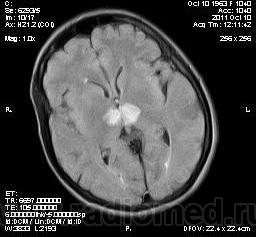

женщина 1963 года рождения. давность заболевания 10 дней.

Билатеральный таламический инфаркт. Либо венозный, либо вследствие закупорки одной из ветвей задней мозговой артерии - ЗМА (вариан развития ЗМА). Но не средней мозговой артерии (СМА). Мне представляеться, что здесь второе... За венозный инфаркт данных не вижу.

MELAS? Чем черт не шутит?

MELAS- по лаколизации очень похоже, но пока нет достоверных данных на него указывающих

Тогда КТ надо еще сделать, для исключения кальцинатов в базальных ганглиях.

Я неприклонен... Инфаркт ЗМА (вероятно, варианта развития левой ЗМА - эмболии, мойа-мойа..).